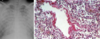

Gross pathology – fibrotic changes in lower lobes, elastic hard consistency, diffuse destruction of lung mesenchyme, multiple air cysts with honeycomb change

Usual interstitial pneumonia (UIP) pattern